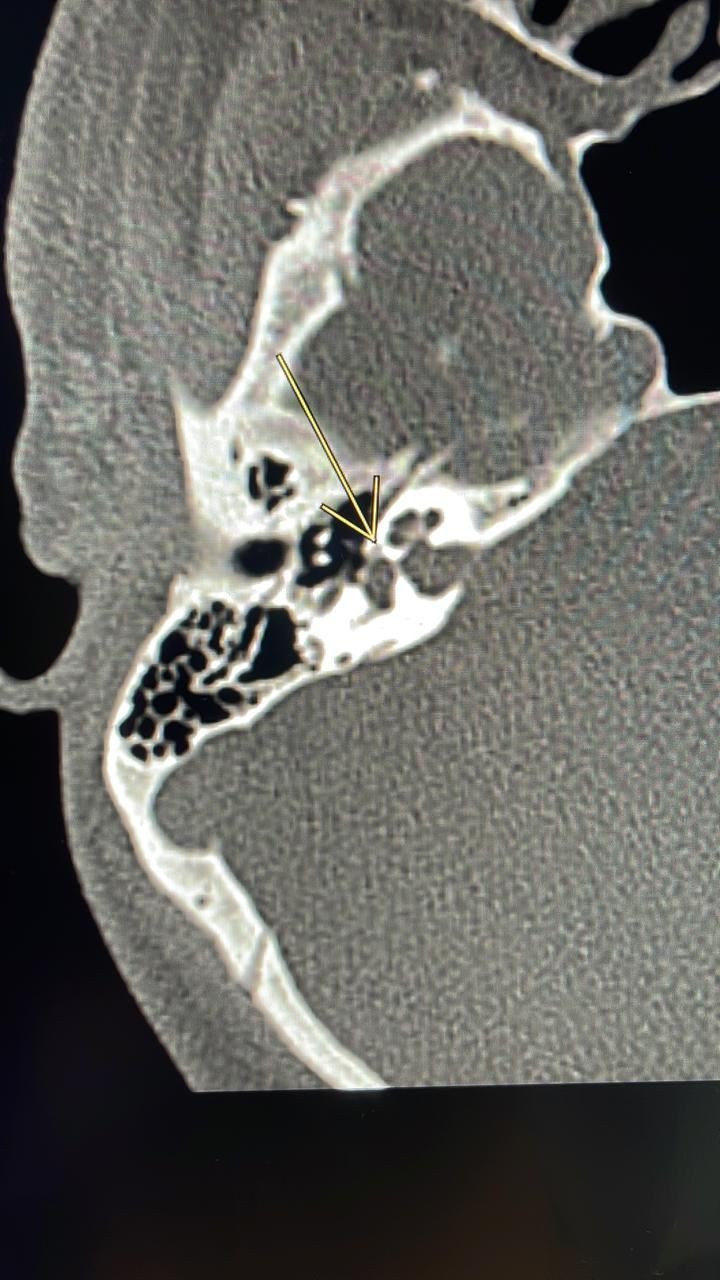

واستقبلت المدينة الطبية المريض الذي كان يعاني من ضعف في السمع وتم إجراء كامل الفحوصات الطبية اللازمة والتي أظهرت نتائجها وجود تصلب عظمة الركاب والذي تسبب بانعدام وجود الاهتزازات التي تنقل الصوت نتيجة نمو العظم حول الصفيحة القدمية لعظمة الركاب مما يتسبب في فقدان تدريجي للسمع.

وأوضح الدكتور فارس الغامدي بأن عملية ثقب عظمة الركاب بالمايكروسكوب هي عملية جراحية يتم فيها إصلاح فقدان السمع التوصيلي الناتج عن تصلب عظام الأذن الوسطى حيث تصبح عظمة الركاب متصلبة وبذلك لا يمكنها الاهتزاز نتيجة نمو العظم حول الصفيحة القدمية لعظمة الركاب ويتسبب ذلك في فقدان تدريجي للسمع، وأضاف بأن عملية ثقب عظمة الركاب تساعد في علاج تصلب الأذن الوسطى عن طريق تجاوز عظمة الركاب المتصلبة بأخرى صناعية.